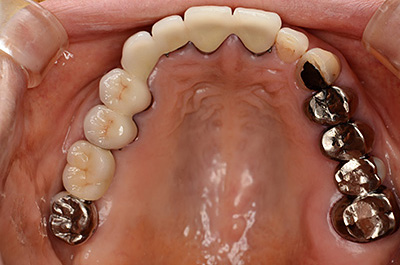

患者さんは他の医院で左下のインプラント治療をしましたが、上の奥歯は骨がないのでインプラント治療はできないとのことで紹介で来院しました。